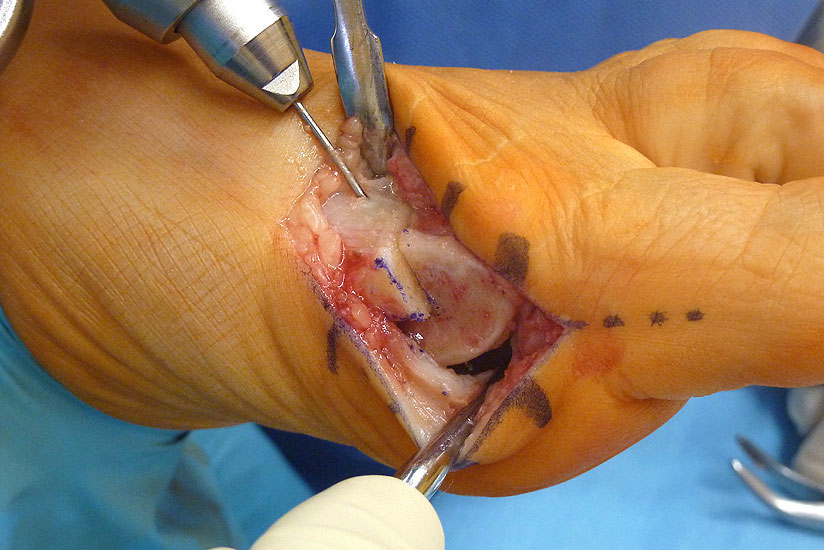

Abbildung 2

Allgemeines Fußinstrumentarium mit Pinzetten, Skalpell(en), Klemmchen, Luer, kleiner Meisel, Seidenschneider, Zange, kleine Langenbeckhaken und Hohmann-Hebel, Präparierschere, kleines Raspatorium und McGlamry Elevator (Abbildung 2)